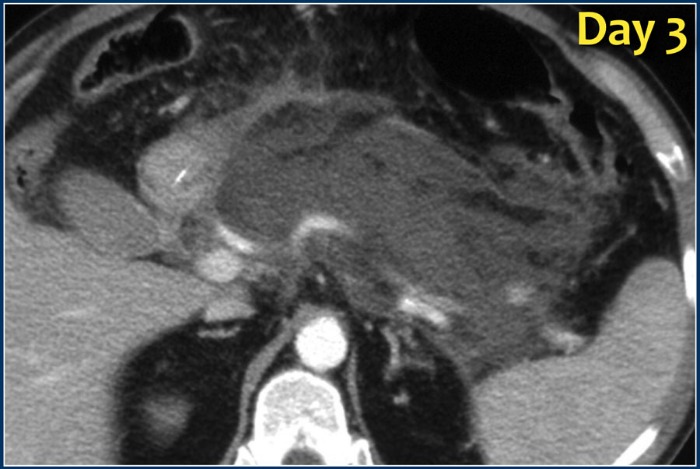

![]()

На аксиальном постконтрастном КТ-скане, сделанном в первый день начала клинической картины железа выглядит диффузно увеличенной, окружающая жировая клетчатка тяжиста. При исследовании, проведенном на третий день вся ткань железы практически не накапливает контрастное вещество (некротизирующий панкреатит). На семнадцатый день можно увидеть сформированный, ограниченный стенкой коллектор с неоднородным содержимым, внутри которого визуализируются пузырьки газа (стрелка) — признак инфицированного некроза.